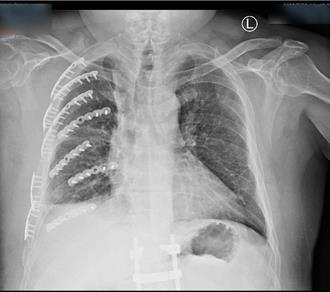

國道事故處理組1名51歲的陳姓工作人員,約1個月前在清除國道上危險物布鉤繩時,遭遊覽車撞傷,造成肋骨斷裂14處、右手橈骨及骨盆腔骨折,經過衛福部彰化醫院胸腔創傷微創重建中心及骨科接連手術後,原本連呼吸都痛、只能盡量憋氣的陳先生終於再展笑容。